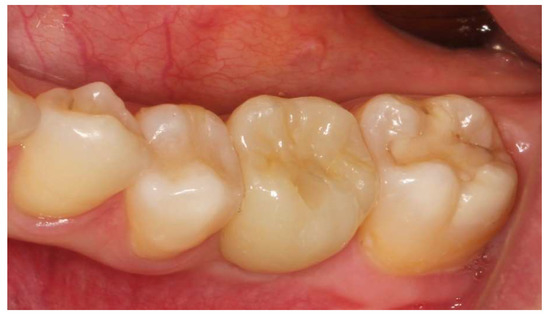

After the integration time, which was 4–6 months for the maxilla and 3 months for the mandible, a clinical and radiological follow-up was performed. Each patient was postoperatively CBCT scanned with the same exposure setting as used for the preoperative evaluation. Further treatment included exposure of the implants and the fitting of healing screws, and the final screw-retained ceramic restorations (Figure 4) were received using digital impressions with a Carestream Dental CS 3600 intraoral scanner.

Figure 4. The screw-retained ceramic crown of tooth 36.